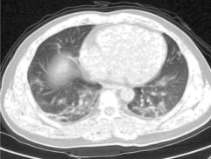

Figure 3 is showing the different stages of enhancement process of one lung image.

Figure 3. Steps of image enhancement